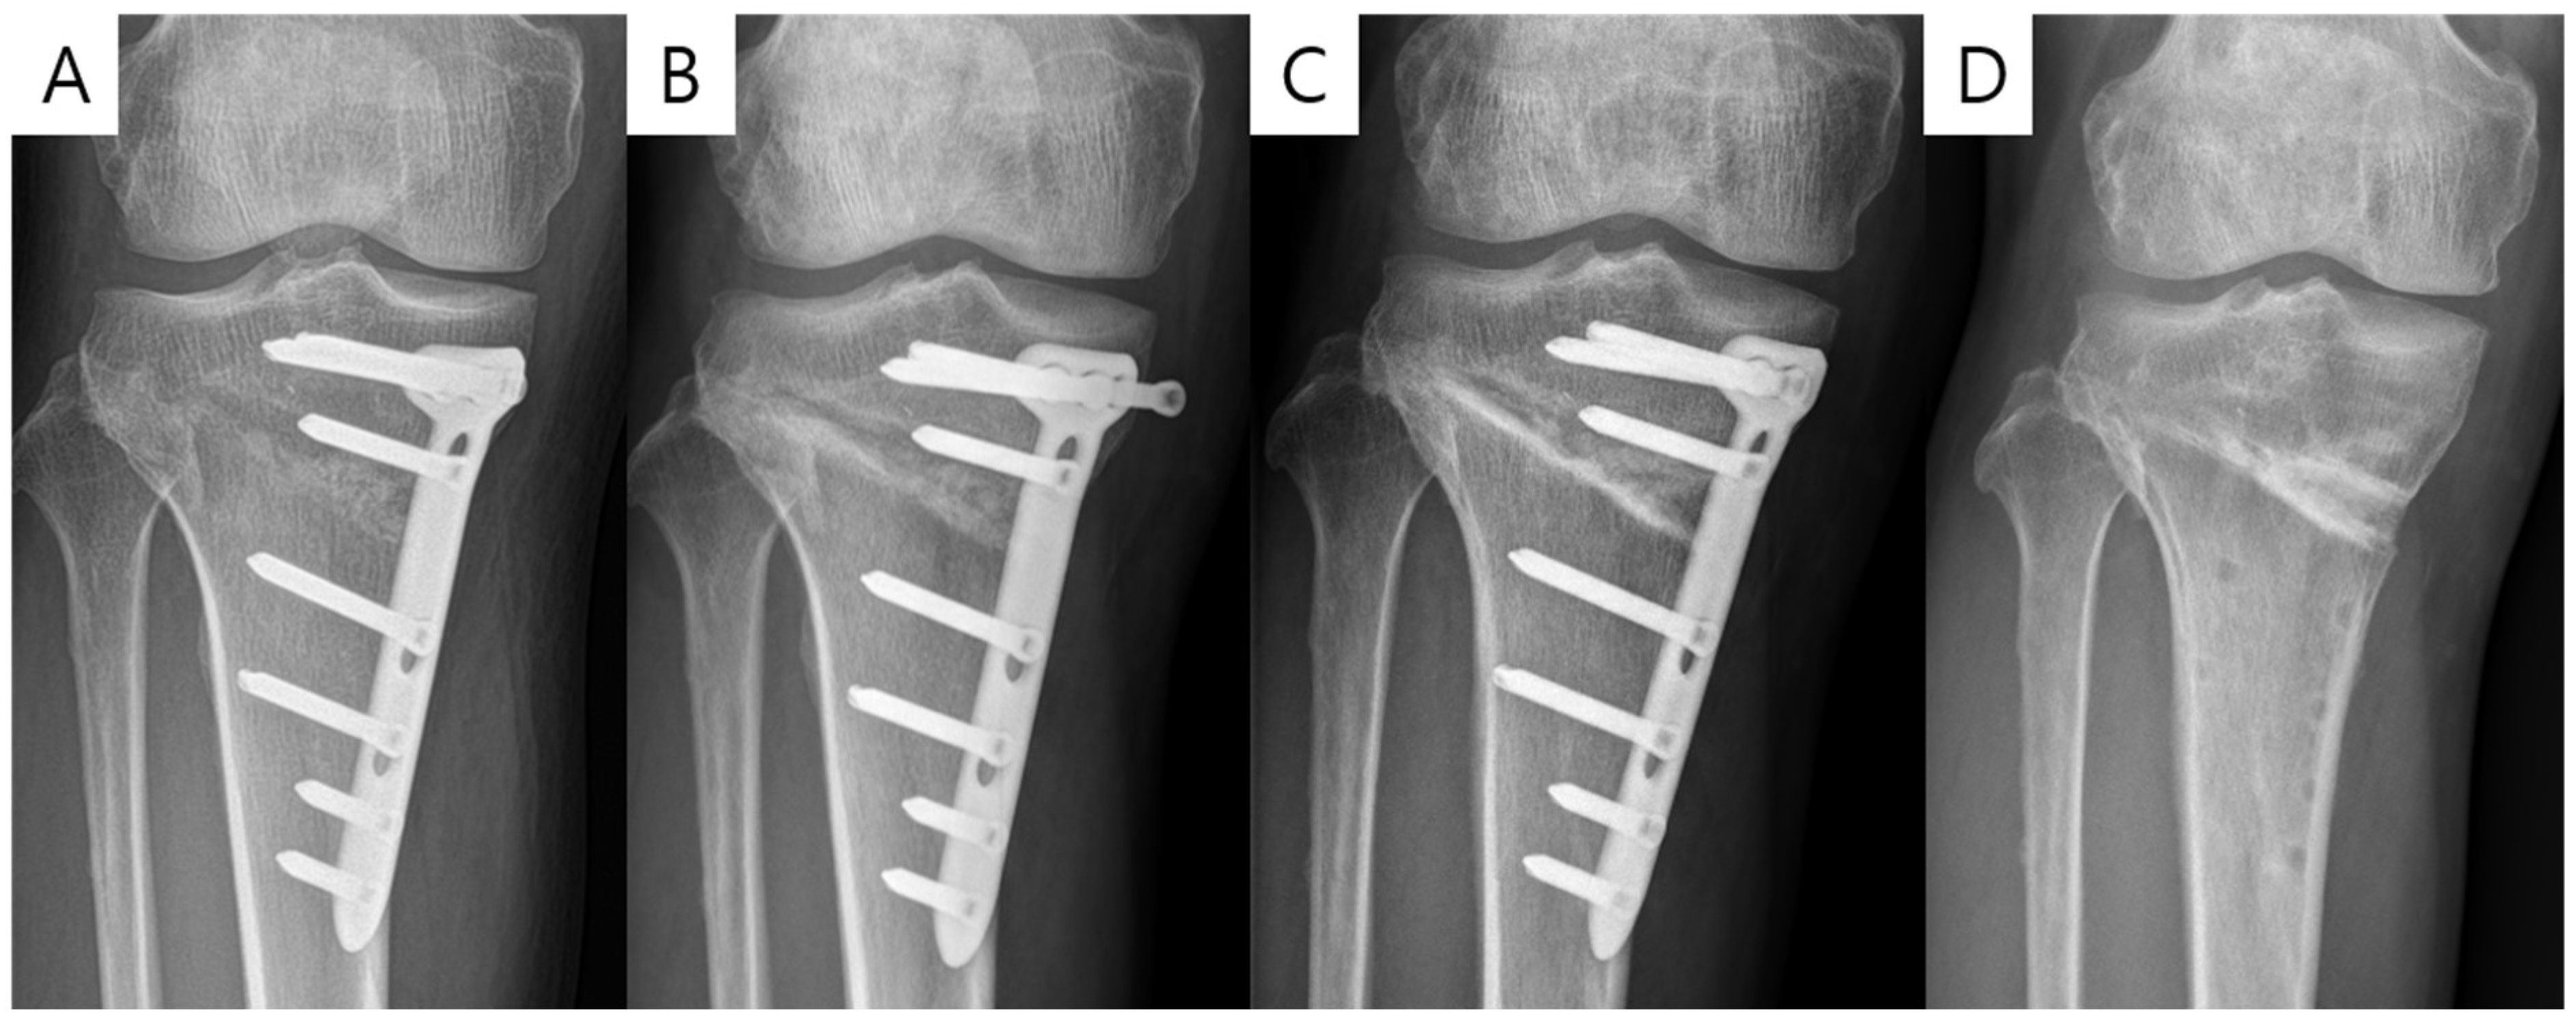

3.2. Comparison of CA Plate and IA Plate